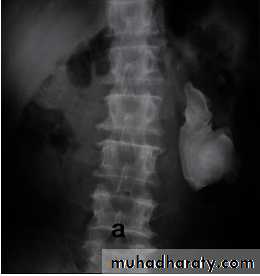

IVU

Normal excretory phase of an IVU (intravenous urogram). This film was taken approximately 10 minutes following IV injection of iodinated contrast material. The kidneys are excreting contrast into non dilated calyces (arrows), renal pelvis (p), ureters (*) and bladder (B).